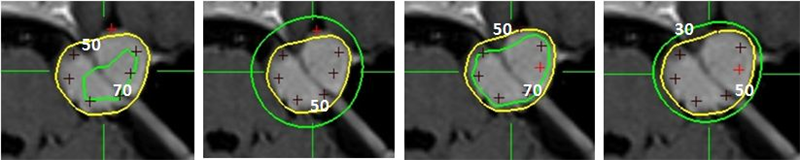

Hình 4: Hình ảnh khảo sát các đường đồng liều 30,50,70.

Bệnh nhân Nguyễn Thị Ng.;   nữ, 52 tuổi, chẩn đoán: U màng não góc cầu tiểu não (T). Chỉ định xạ phẫu dao gamma quay (RGK) liều 18Gy”

• 50% đường đồng liều xung quanh khối u

• Thể tích của đường đồng liều 70% của kế hoạch (A) nhỏ hơn kế hoạch (C)

• Thể tích của đường đồng liều 30% của kế hoạch (B) rộng hơn kế hoạch (D)